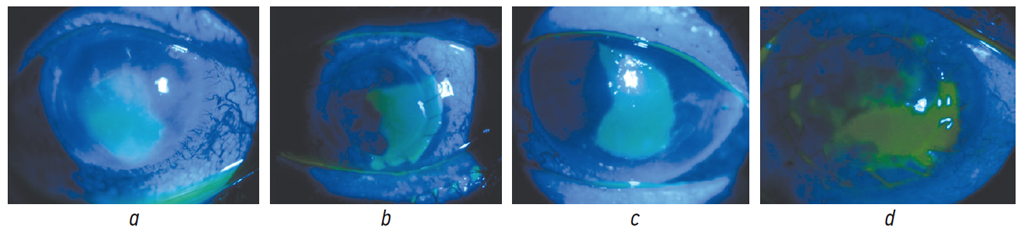

The problem of prolonged re-epithelialization after keratoplasty remains unsolved and urgent. The term PED is commonly used to characterize persistent, non-healing lesions of the corneal epithelium that persist 2 weeks after the standard therapy [21, 22]. Photos of patients with PED during the standard therapy after various types of keratoplasty are presented in Fig. 1.

Fig. 1. Biomicroscopy of the anterior segment with corneal fluorescein staining under focal illumination in blue cobalt light on Day 15 after keratoplasty: a – Descemet’s stripping automated endothelial keratoplasty; b – penetrating keratoplasty; c – Descemet’s membrane endothelial keratoplasty; d – automated anterior lamellar keratoplasty

Рис. 1. Биомикроскопия переднего отрезка глаза с окраской роговицы флюоресцеином при фокальном освещении в синем кобальтовом свете на 15-е сутки после кератопластики: a — автоматизированная эндотелиальная кератопластика с удалением десцеметовой мембраны; b — субтотальная сквозная кератопластика; c — эндотелиальная трансплантация десцеметовой мембраны; d — автоматизированная передняя послойная кератопластика